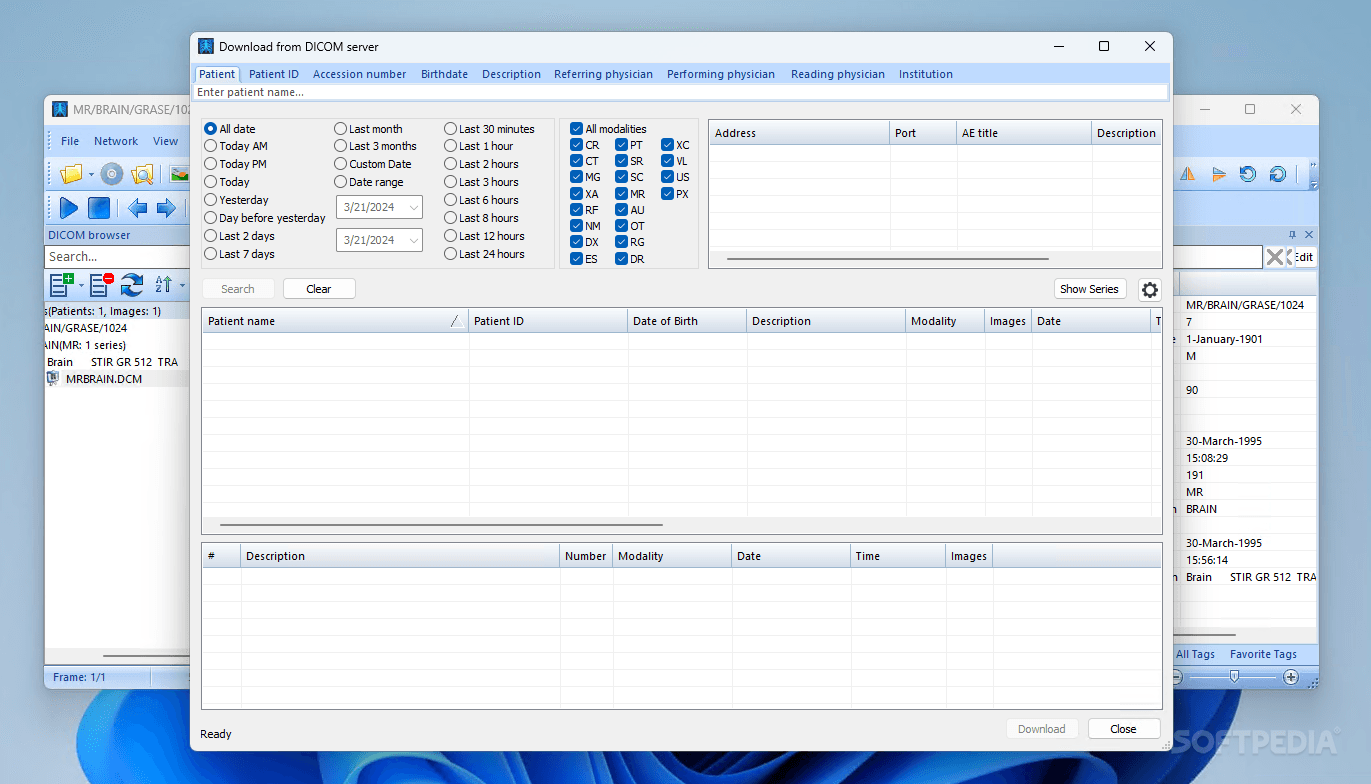

Лазерная камера сетевая для печати изображений на пленке стандарт dicom